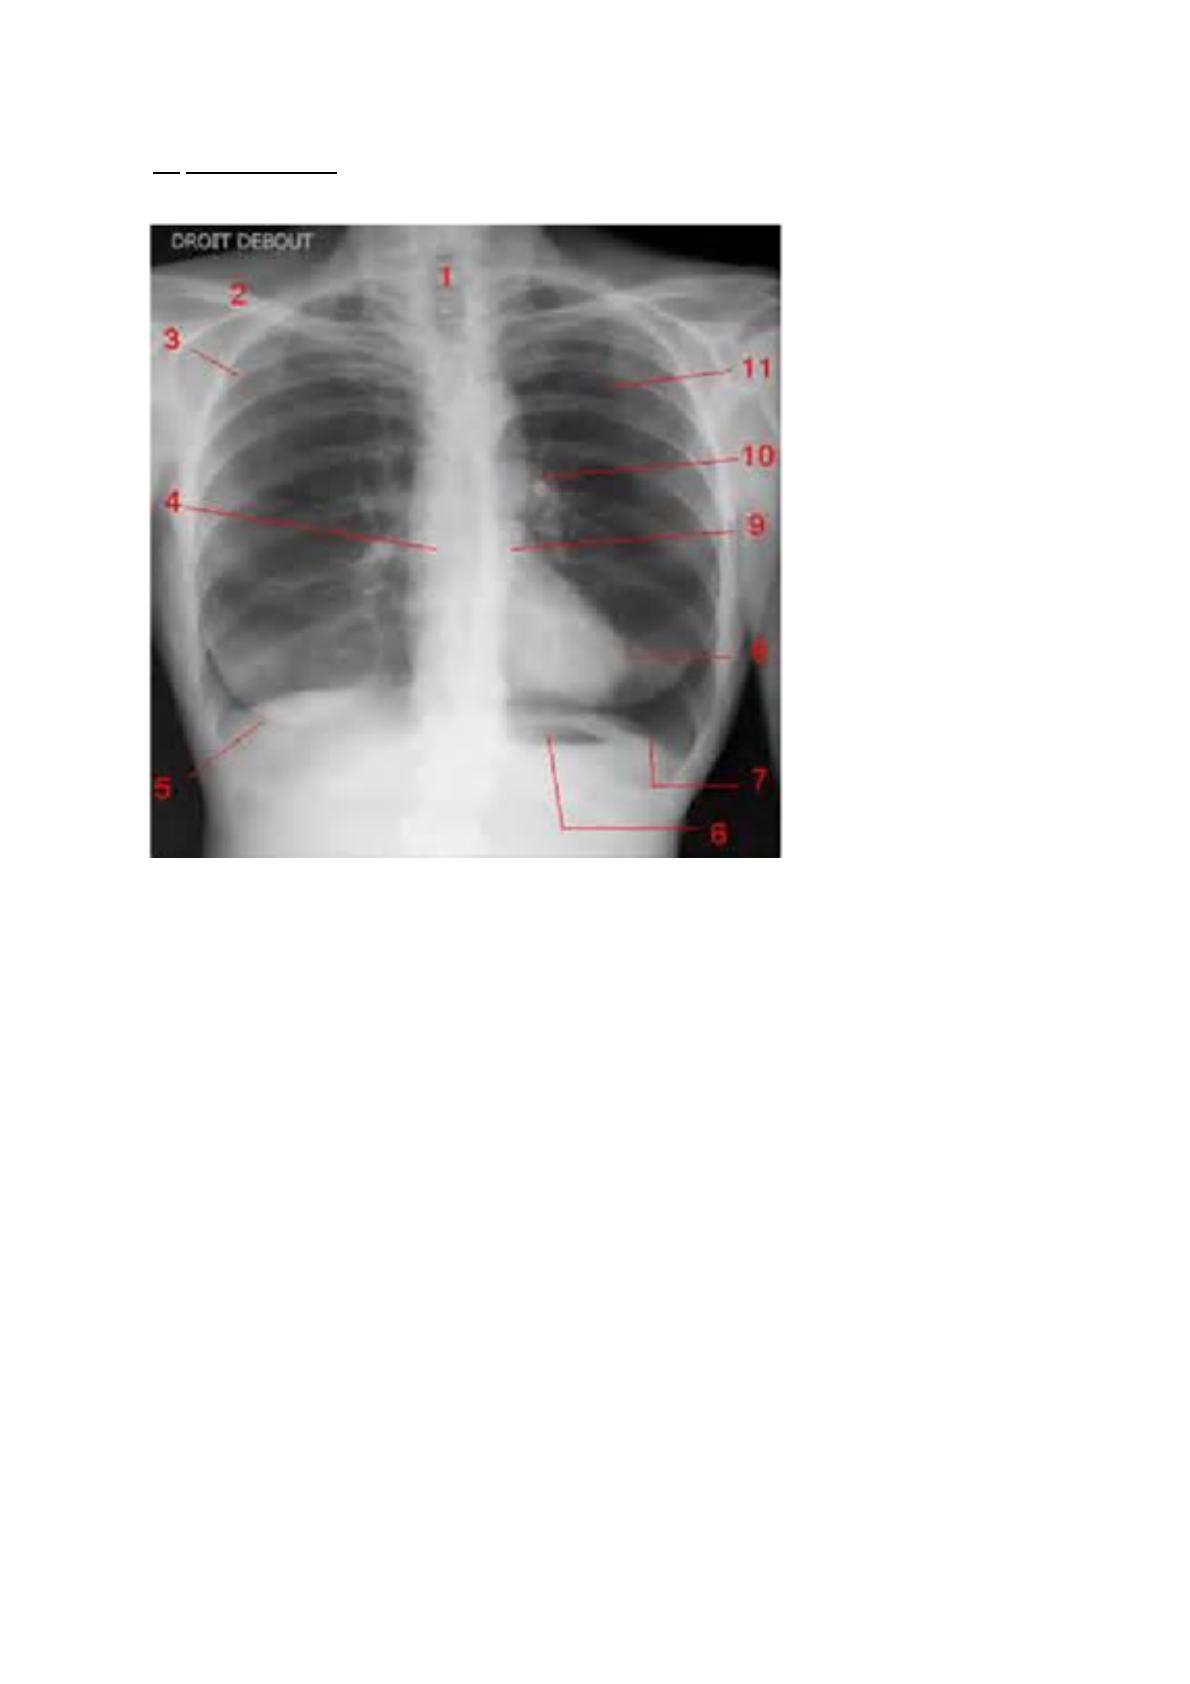

2) Application

1) Trachée

2) Clavicule droite

3) Cote

4) On voit mieux les corps vertébraux que le sternum à cause de leurs densités. Ici ce

n'est pas le sternum mais un organe : le coeur avec son oreillette droite.

5) Glande mammaire (sein dense donc femme jeune)

6) Estomac, avec sa poche à air gastrique sous coupole diaphragmatique gauche => ce

qui permet de dire qu’elle était debout.

7) Coupole diaphragmatique gauche

8) Cœur ventricule gauche

9) Artère pulmonaire

10)Aorte, si calcifiée : athérome formant une grosse boule blanche (à la radio) au niveau

de la crosse.

11) Champs pulmonaire ou bord interne de la scapula : ligne blanche à la verticale (d’où

la position lors d’une radio pour dégager les scapulas latéralement).

Pour analyser d’une radio, on regarde d’abord le contenant (cage thoracique :

sternum,cote,vertèbre) d’abord puis le contenu (poumons cœur)